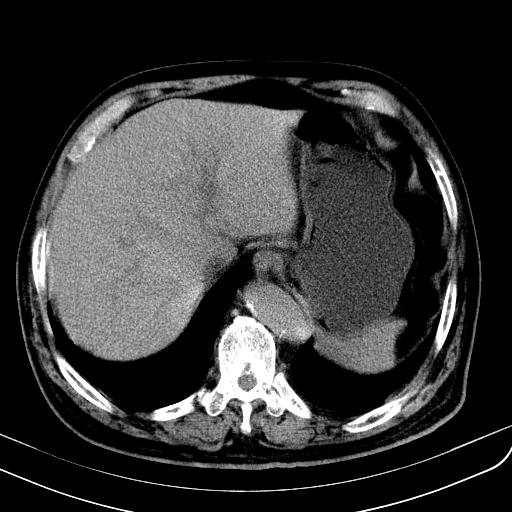

胃底靠近胃大弯处可见一圆形软组织影,直径为3.45cm,ct值约为30.1hu